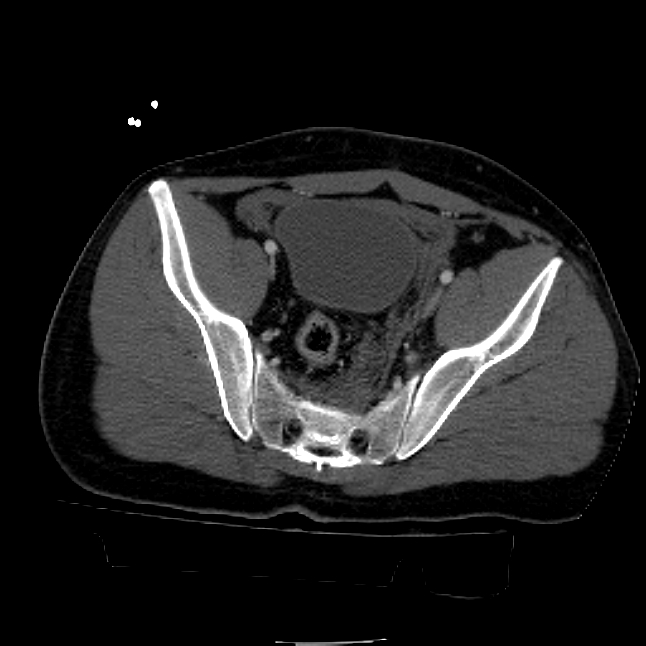

25 yo brittle diabetic, became hypoglycemic and passed out on his motorcycle. Sustained bilateral lateral Hoffa fractures with associated LCL injury on the right and right distal radius fracture. I have questions regarding his pelvic ring/acetabular fracture on the left. Appears to be a very low posterior column fracture with associated posterior wall, marginal impaction. Superior and inferior rami fractures as well on the left giving him a floating segment of inf ramus/ischium/posterior column, but no detectable posterior ring injury. Should the posterior column/posterior wall fracture be addressed surgically because of the marginal impaction? Or is this fracture low enough to be treated non-operatively? I appreciate the input.

It's an interesting case. The plain films show the impaction, but most of the joint looks pretty good. The CT cuts look awful, though.

The impaction is so big I don't think I would ignore it. It IS down low, but it takes up almost the whole southern hemisphere of his joint.